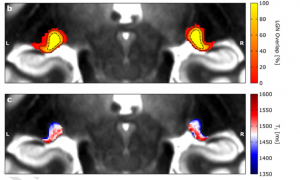

Mehr erfahren zu: "Glaukom: Neues Deep-Learning-Modell hilft beim automatisierten Screening" Glaukom: Neues Deep-Learning-Modell hilft beim automatisierten Screening Eine Gruppe japanischer Forscher der Universität Tohoku hat ein neues Deep-Learning(DL)-Modell entwickelt, welches Bildauffälligkeiten im Zusammenhang mit Erkrankungen des Auges präzise und schnell erfasst.

Mehr erfahren zu: "Glaukom: Intelligente Kontaktlinse zur Echtzeit-Überwachung des Augeninnendrucks" Glaukom: Intelligente Kontaktlinse zur Echtzeit-Überwachung des Augeninnendrucks Ein Forschungsteam um Dr. Yangzhi Zhu vom Terasaki Institute for Biomedical Innovation (TIBI), USA, hat eine intelligente Kontaktlinse entwickelt, die den Augeninnendruck mithilfe von künstlicher Intelligenz (KI) in Echtzeit überwacht […]